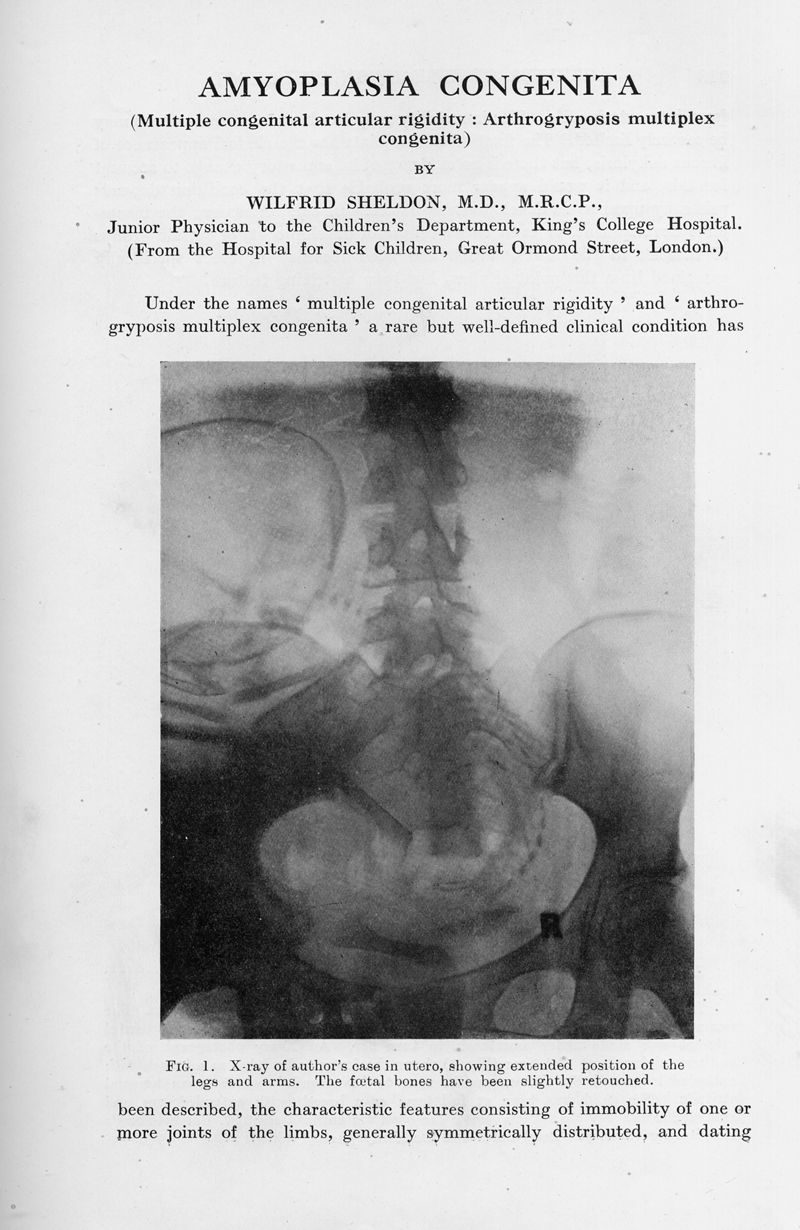

Amyoplasia congenita. (Multiple congenital articular rigidity : Arthrogryposis multiplex congenita)

In : Archives of Disease in Childhood, 1932, Vol. 7, pp. 117-36